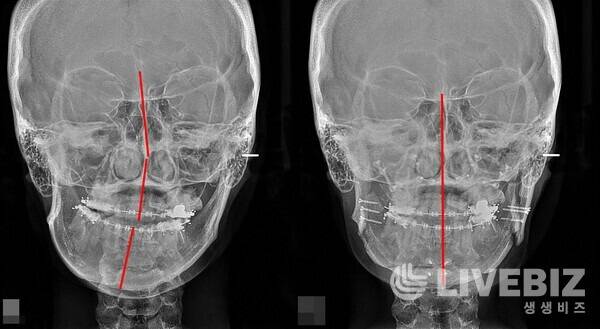

두 번째 적응증은 안면 비대칭이다. 안면 비대칭 중에서도 특히 얼굴의 중심축이 휘어 있는 비대칭의 경우 턱관절 기능과 관련이 있어 근본적인 치료를 위해서는 얼굴의 중심축을 바로잡아 주기 위해 양악수술이 이뤄진다.